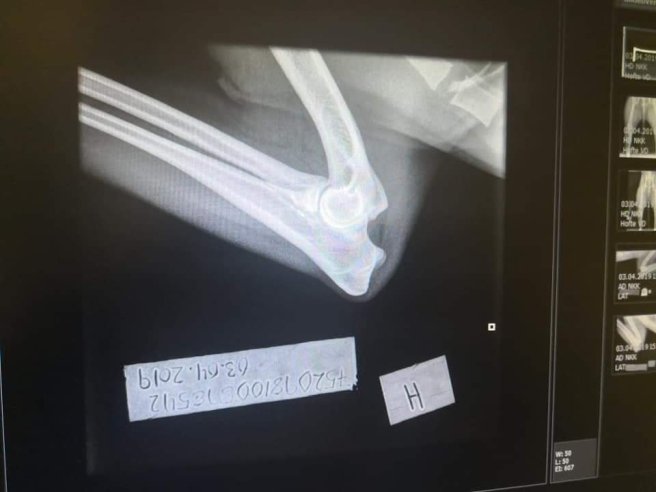

Hinnih fria armbågar ❤ april 16, 2019april 16, 2019 ~ kelpiecarro Grattis Hanne och Hinnih ❤ som också sedan tidigare är röntgad med A på höfter Dela detta: Dela på X (Öppnas i ett nytt fönster) X Dela på Facebook (Öppnas i ett nytt fönster) Facebook Gilla Laddar in … Relaterade